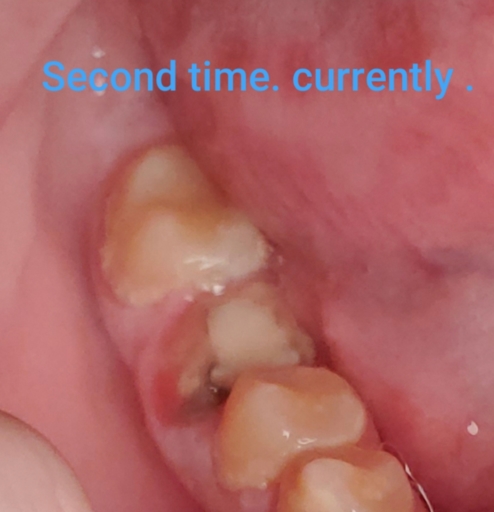

Sometimes it is necessary to adjust the opposing tooth when a new restoration is placed in order to maintain the integrity of the restoration.  However, if several teeth are being adjusted, there may be an additional reason why.  These adjustments to your tooth structure should be very minimal and should not cause any discomfort.  Initially, some cold sensitivity may arise, but should subside quickly.  The crown in the picture provided, appears to be similar to the size and shape of tooth #30.  When a dentist finds it necessary to adjust adjacent teeth, your permission should be given prior to the procedure.  If your teeth are causing discomfort and you have additional questions regarding your treatment, you should speak to your dentist and allow he/she to provide feedback and an explanation for the additional treatment.